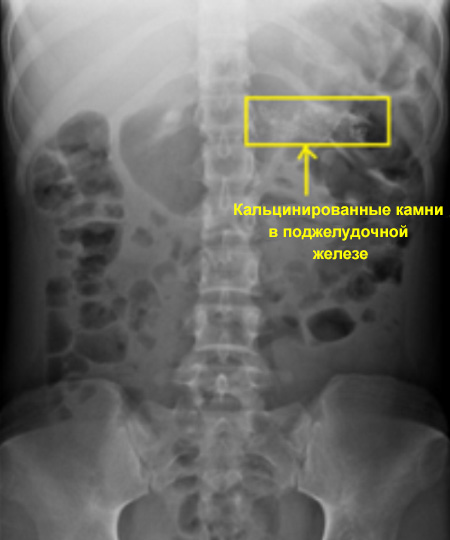

Кальцинированные камни в поджелудочной железе

Рентгенологическая картина при остром панкреатите характеризуется: